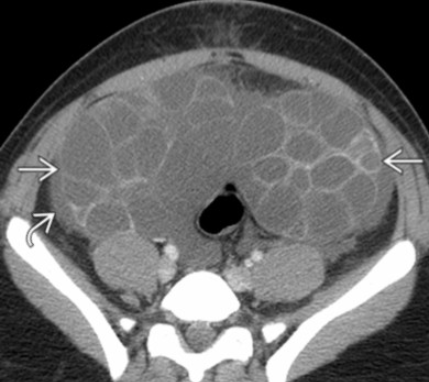

Mucinous Cystadenoma

• Multiloculated

• Thin walled with septa

• Simple and/or complex fluid